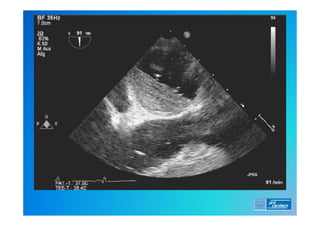

6) Ecocardiograma (TT e TE)

Diagnóstico . 0) EXAME FÍSICO 1)ECG (alterações frequentes ?) 2) RX de Tórax (o que esperar ?) 3) Laboratório (o que é importante ?) 4) D Dimero 5) Doppler Venoso MMII 6) Ecocardiograma (TT e TE) 7) Angio TC 8) Cintilografia Pulmonar (Ventilação/Perfusão) 9) Angio RM 10) Arteriografia